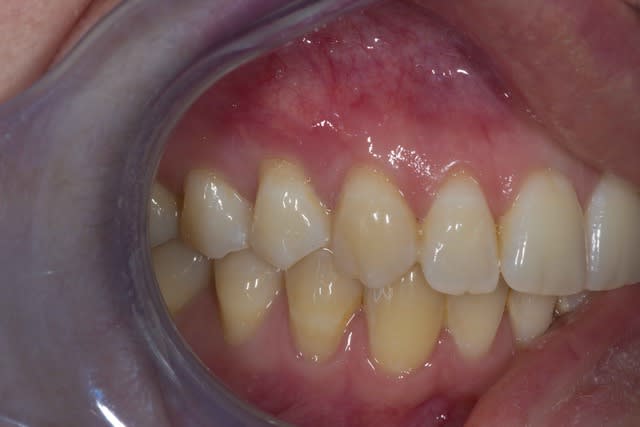

La technique de tunnélisation est utilisée avec de très bons résultats par Aroca, Sculean, Zuhr, Hürzeler. La traction coronaire des tissus gingivaux est indispensable pour optimiser au maximum le recouvrement radiculaire.

Le recouvrement radiculaire doit en effet être surcorrigé (1 à 2 mm) pour compenser la contraction tissulaire qui est inévitable.

C'est justement ce surcorrigé qui est très difficile à obtenir avec la technique du tunnel. Il existe des techniques de sutures que Sculean et Zuhr utilisent afin de gérer tout ça, mais vous ne semblez pas les utiliser. L'inconvenient est que ce tracté coronaire entraine très souvent un volume papillaire trop important et un plissé tissulaire qui esthétiquement peut être préjudiciable.

En terme d'analyse de résultat, une chirugie mucogingivale de recouvrement radiculaire n'est considérée comme un succÈs uniquement quand 100% de la récession est recouverte. Même si un recouvrement de 80-90% peut être considéré dans certains cas comme un très bon résultat, c'est par le patient considéré comme un échec complet si les 10% de racine non recouverte sont toujours sensibles ou si le joint dentoprothéique est toujours visible !

Les récessions que Tillc et Clio ont opéré auraient dû être totalement recouvertes. Et cela était parfaitement prévisible si un LDC modifié avait été pratiqué.

J'ai pratiqué toutes ces techniques chirurgicales de très nombreuses fois et je recommande largement d'utiliser le LDC modifié plutôt que la technique du tunnel.

Il y a toujours dans notre profession une tendance par certains de préconiser des techniques difficiles et de faire croire que la gestion de certains problèmes n'est pas à la porté de tout chirurgien dentiste. La technique du tunnel en est un parfait exemple. À résultat équivalent et en terme de compléxité d'exécution sur une échelle de 0 à 10 (où 0 est le plus simple et 10 le plus compliqué), la tunnélisation est un 8 alors que le LDC modifié est un 5.

Je ne comprends donc pas Aroca, Sculean et Hürzeler sur ce point. Je rejoins sur ce point Zucchelli.

Faite simple et tout ira beaucoup mieux !!